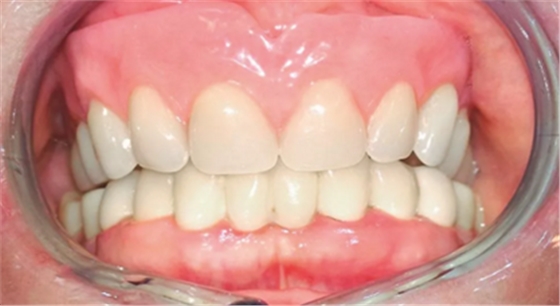

在對義齒的位置進行最終調整后,制作覆蓋義齒(圖11)。試戴覆蓋義齒,達到咬合平面,臨時決定暫時僅安裝4個Preci附件中的2個,以便于患者更容易適應義齒。3周后將所有覆蓋義齒中的配件安裝完畢。

(圖11)